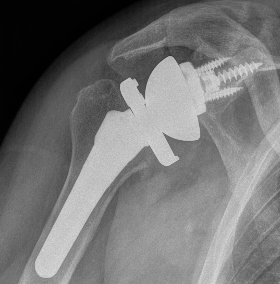

Glenoid component

Metaglene / baseplate

Depuy Synthes Delta Xtend

Design

- uncemented

- coated central peg

- secured by compression non locking screws + locking screw

- +/- variable angle to allow inferior screws along scapular spine / superior screw into coracoid

Glenosphere

Press fit / morse taper onto baseplate

Lateralized / thicker options - limit scapular notching

Eccentric options - shift center of rotation inferior, limiting scapular notching